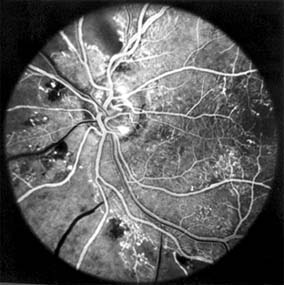

Retinal Branch Vein Occlusion (new window  Figure 15-8)

Occlusion of a branch vein should be viewed as part of the spectrum of central retinal vein occlusion. Investigations are similar in the two conditions, but arterial disease-particularly hypertension-is common. Branch retinal vein occlusion occurs more frequently in the superotemporal and inferotemporal regions and particularly at sites where arteries cross over veins, and only rarely where veins cross over arteries.

Figure 15-8

Figure 15-8: Retinal branch vein occlusion. The affected segment of retina shows changes of reduced perfusion. This results in irregularity of the arterioles and veins, areas of capillary closure, and dilated capillaries with microaneurysms.

The value of laser treatment in the management of the complications of branch retinal vein occlusion is discussed in Chapters 10 and 24.